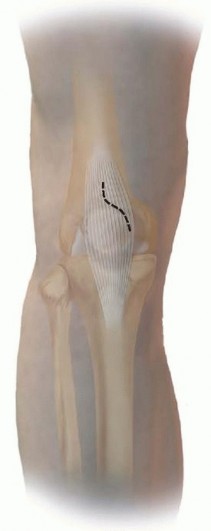

Intramedullary nailing techniques are typically used for closed and open displaced diaphyseal tibial fractures. The indications for intramedullary nailing can be extended to proximal and distal metaphyseal tibia fractures, including those associated with simple articular involvement. Both traditional peripatellar and semiextended approaches are used to attain the entry site for nailing all levels of tibial fractures. ## ANATOMY The triangular-shaped proximal tibia is narrowest medially, and the proximal medial cortex tibia is obliquely oriented to the frontal plane. The medullary canal of the tibia exits at the margin of the lateral articular facet. As a result of this complex proximal anatomy, there is less sagittal plane space for an intramedullary nail within the tibia metaphysis with a medial or central insertion path. With a medial start site, the anteromedial metaphyseal cortex can deflect the nail and create a valgus deformation. Due to these factors, a tendency toward a more lateral start site is favored. The patellar tendon inserts on the tibial tubercle and extends the proximal fracture segment in proximal fracture patterns. This displacement is accentuated with further flexion of the knee, which typically is required to attain the proper starting point for intramedullary nailing ( FIG 1A). Gerdy tubercle—the origin of the anterior compartment muscles and insertion site of the iliotibial band—is palpable along the proximal lateral tibia. In addition to the deforming forces of the patellar tendon, the anterior compartment muscles and the iliotibial band contribute to the shortening and valgus deformity typically seen with more proximal fractures. The anterior tibial crest corresponds to the vertical lateral surface of the tibia. When it is palpable, it is an excellent reference for the anatomic axis and nail path ( FIG 1B). The anteromedial tibial surface is subcutaneous and often is the site of traumatic open wounds. The anterior neurovascular bundle and tibialis anterior tendon are at risk with anterior to posterior distal interlocking screw paths; internal rotation of the nail may decrease the risk of iatrogenic nerve injury 3 ( FIG 1C). The Hoffa fat pad and intermeniscal ligament are commonly injured during all tibial intramedullary nail insertion techniques, especially during lateral parapatellar and patellar tendon-splitting approaches. 27, 34 ## PATHOGENESIS Tibial shaft fractures may occur from high-energy mechanisms of injury, as when a pedestrian is struck by a motor vehicle. Many fractures, however, result from lowenergy mechanisms such as simple falls in elderly patients or those with poor bone quality or sports-related injuries (common in soccer players) in younger patients. 6 In this low-energy fracture group, elderly patients are more likely to have comminuted and open fractures due to simple falls. ## NATURAL HISTORY The long-term outcome of tibial malunion is not clearly defined in the trauma literature. A weak association is seen between a tibial shaft fracture malunion and ipsilateral knee and ankle arthritis. 12, 19, 32 Knee pain is reported in up to 58% of cases after intramedullary nailing. This pain typically is anterior, associated with activity, and exacerbated by kneeling activities. 6, 11 Knee pain improves in about 50% of patients after hardware removal. 6 Attempts to detect a correlation between start sites and knee pain have been inconclusive, and comparative evaluations between traditional start sites and semiextended start sites (ie, suprapatellar) are underway. ## PATIENT HISTORY AND PHYSICAL FINDINGS Understanding the mechanism of injury and the environment in which the injury occurred is important for evaluating a patient's risk for associated injuries and compartment syndrome. In open fractures, it can help determine the choice of prophylactic antibiotic therapy. All patients who sustain tibial shaft fractures from highenergy mechanisms should undergo standard advanced trauma and life support (ATLS) protocol to have a thorough examination for life- and other limb-threatening injuries. Seventy-five percent of patients with open tibia fractures have associated injuries. 1 To evaluate a patient's risk for potential complications, other medical conditions should be investigated, including a history of diabetes mellitus, renal disease, inflammatory arthropathies, tobacco use (which increases healing time by up to 40%), and peripheral vascular disease. 4 It also is important to find out about the patient's normal activities and employment requirements to give them a reasonable expectation for when they will be able to resume those activities. Pain at the fracture site, swelling, and deformity are common findings in patients with tibial shaft fractures. A thorough examination of the skin is important to avoid missing open fracture wounds. Evaluation of the soft tissue envelope for abrasions, contusions, and fracture blisters can help determine whether 548 definitive treatment can be done primarily or if a staged or delayed approach is required.

### FIG 1 • A. The metaphyseal segment extends with knee flexion secondary to the pull of the patellar tendon. B. The anterior tibial crest is palpable and represents the vertical lateral border of the tibia. Palpation of the crest can help aid in starting wire orientation. C. Anterior neurovascular structures are at risk during anterior placement of distal interlocking bolts; internal rotation may decrease the risk of arterial injury. A detailed neurovascular examination is critical to avoid the devastating complications associated with compartment syndrome, which can occur in both closed and open fractures (see Cha 53). ## IMAGING AND OTHER DIAGNOSTIC STUDIES Full-length anteroposterior (AP) and lateral plain radiographs are necessary to adequately evaluate the tibia and fibula. Complete orthogonal views of the tibia and fibula help evaluate for concurrent fractures or dislocation and any preexisting deformity or implants. Orthogonal radiographic views of the knee and ankle are required to rule out articular involvement. Axial computed tomography (CT) scan can be used for proximal and distal fractures to rule out intra-articular fracture extension. Nondisplaced fracture lines are common. Gunshot wounds may merit CT evaluation to rule out intra-articular bullet fragments and intra-articular fracture extension. Magnetic resonance imaging (MRI) is not useful for most diaphyseal or metadiaphyseal fractures. Ankle-brachial index (systolic pressure in injured leg below injury divided by systolic pressure of the brachium) after fracture reduction should be used to rule out vascular injuries in severely displaced fractures or fractures with severe soft tissue injury. Values of less than 0.9 may be indicative of vascular injury, requiring further investigation. 18 549 Compartment pressure evaluation with a commercially available handheld single-stick monitor or with a sideported catheter connected to a pressure monitor (using the arterial line setup) is indicated in patients who have severe or increasing swelling and are not able to comply with physical examination and questioning. Observe for early signs of compartment syndrome in all patients with tibial diaphyseal fractures. Open fracture does not preclude development of compartment syndrome. Measure the pressure difference between the diastolic pressure and the intracompartmental pressure—a differential value of less than 30 mm Hg is considered an indication for a four-compartment fasciotomy. 17 ## NONOPERATIVE MANAGEMENT Nonoperative management is indicated in ambulatory patients for closed and open fractures that do not require flap coverage and that do not present with excessive initial shortening or unacceptable angulation when a cast is applied ( FIG 2). An intact fibula with an axially unstable fracture pattern (ie, short oblique, butterfly fragment, or comminuted) is at risk for shortening and varus deformities and is a relative contraindication to nonoperative management. A higher rate of malunion and nonunion with nonoperative management is seen in higher energy fractures. 2, 9 Joint stiffness, especially hindfoot, is common with all forms of prolonged immobilization. 7, 22 Initial treatment includes ˜2 weeks of a long-leg splint, then a long-leg cast for 2 to 4 weeks. When the initial swelling has subsided, the patient is graduated to a patellar tendon or functional brace. Weight bearing is allowed and encouraged.